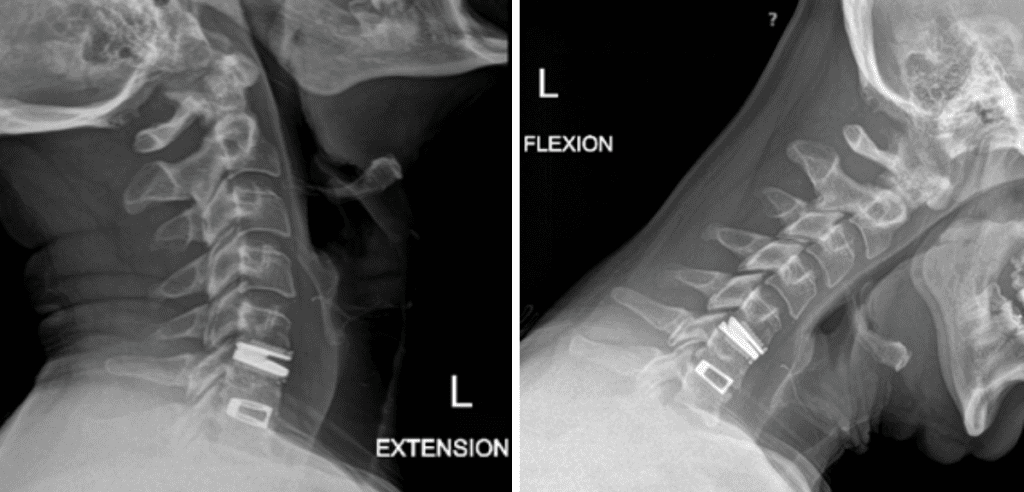

Revision Surgery Treats Intractable Neck Pain & Cervical Deformity

Author: Benjamin R. Cohen M.D., F.A.A.N.S., F.A.C.S., Read More!